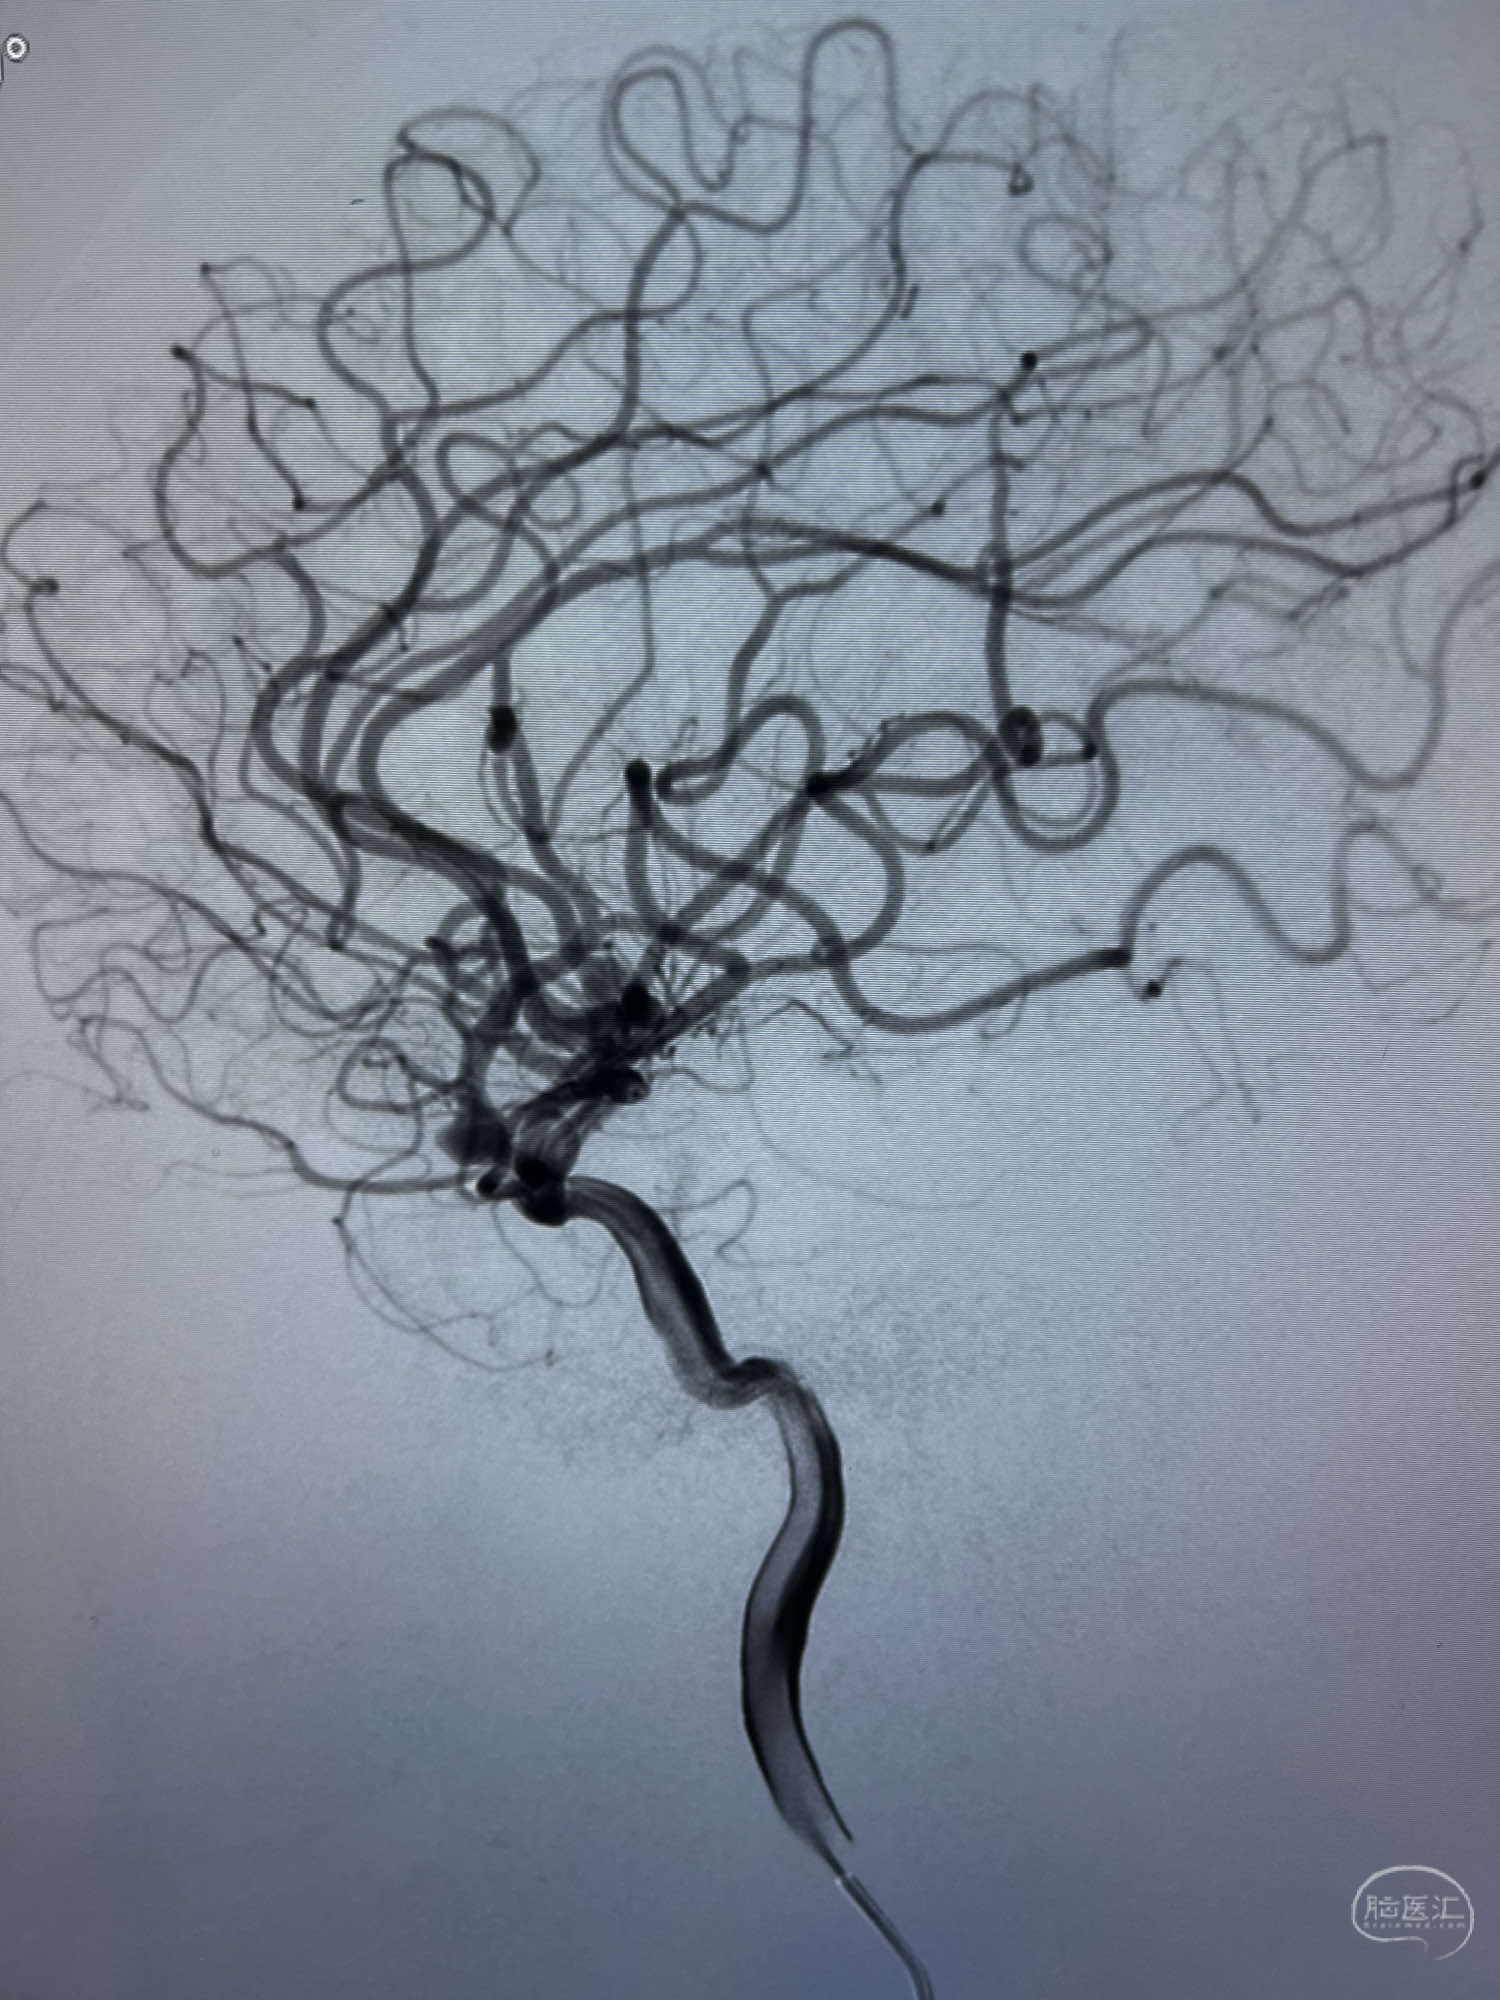

DSA示:左侧颈内动脉眼动脉段以远闭塞,后交通动脉开放,椎基底动脉通过后交通动脉代偿左侧大脑中动脉区域,右侧发出双侧大脑前动脉,右侧大脑中动脉M1末端宽颈动脉瘤,大小约4.3mmx4.6mm。

6F Neuromax➕6F115cm 心玮中间导管建立路径,sychro14微导丝➕VIA21超选至动脉瘤体内近中部,WEB5mmx3mm植入动脉瘤。

WEB瘤内扰流装置5mmx3mm经过“种子、萌芽、开花”三个阶段,打开后良好贴壁,动脉瘤内血液滞留,载瘤动脉通畅。WEB一步到位,通过瘤内扰流的方式起到栓塞动脉瘤的作用,避免了应用支架保护分支血管,简化了操作步骤,降低了术中血栓及出血的风险。